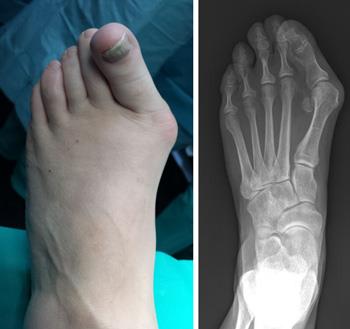

Because bunions vary in shape and size, there are different surgical procedures performed to correct them. In most cases, bunion surgery includes correcting the alignment of the bone by cutting and shifting the bones. This will most likely require the placement of surgical hardware (plates and screws) as well as repairing the soft tissues around the big toe.

To help plan your procedure, your doctor may order special foot X-rays. These X-rays should be taken in a standing, weightbearing position to ensure your doctor can clearly see the deformity in the foot. These special X-rays assist your doctor in making decisions about where along the bone to perform an osteotomy to provide enough corrective power to straighten the toe.